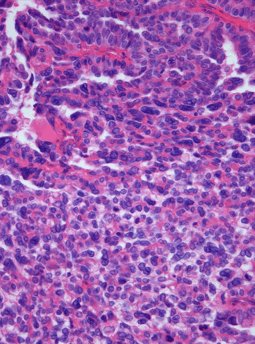

Photomicrograph of hematoxylin-eosin stained section of a choroid plexus carcinoma (grade III WHO) at 400x magnification. | |